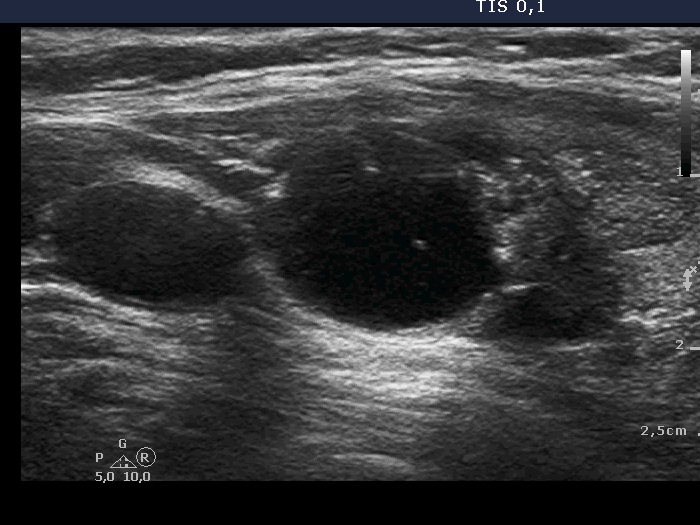

Ultrasound. The thyroid was echonormal. There was a mixed nodule in the ventral part of the left lobe. The lesion presented a moderately hypoechogenic solid part and different types of hyperechogenic figures including several caused by posterior back wall enhancement, comet-tail artifacts and non-specific figures corresponding to connective tissue.

Ultrasound. There was one important change compared with the previous exams. A lobulation has appeared at the lower part of the lobe. This portion was solid and had punctate echogenic foci.

The ultrasound presentation was also remarkable. First, there are no signs of a capsule which decreases the likelihood of a follicular tumor to less than 5%. Second, the nodular area is composed of multiple discrete lesions which itself is a relatively specific sign of a hyperplastic nodule (see video).

The interpretation of tiny hyperechogenic granules is not always unequivocal and non-specific hyperechogenic granules are frequently misinterpreted as microcalcifications.

This case illustrates the issue of differential diagnostic or intranodular figures: granules occurring in the presence of connective tissue, colloid crystals and figures caused by posterior back wall enhancement all may be misinterpreted as microcalcifications as happened in this patient.